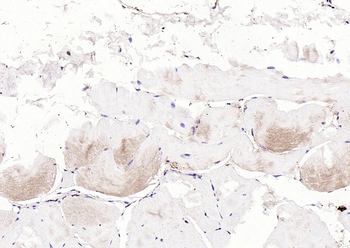

50 μl, 100 μl - KLF4 Recombinant Rabbit Monoclonal Antibody [orb608075]Featured

FC, ICC, IF, IHC-Fr, IHC-P, WB

Human, Mouse, Rat

Rat

Rabbit

Recombinant

Unconjugated

200 μl, 50 μl, 100 μl - Featured